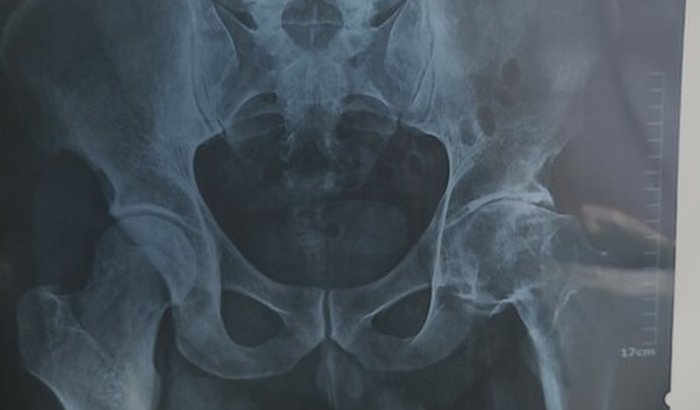

Em 2012 tive um deslizamento da capa do fêmur aonde fui submetido a fazer a primeira cirurgia colocando no lugar e travando com um pino.Dois anos depois fiz outra cirurgia para retirar o pino mais infelizmente deu um desgaste aonde o pino estava em contato e desde lá estou esperando para que o dia da próxima cirurgia resolva meu problema que seria uma protese inclusive muito cara mais de 30 mil reais, mas felizmente aonde eu trabalho o convênio cobre a protese só que ainda falta alguns detalhes a remédios,alguns exames e o tempo que estarei parado.Venho aqui pedi essa ajuda pra realizar esse feito e não sentir mais dor e sim ter uma vida normal.